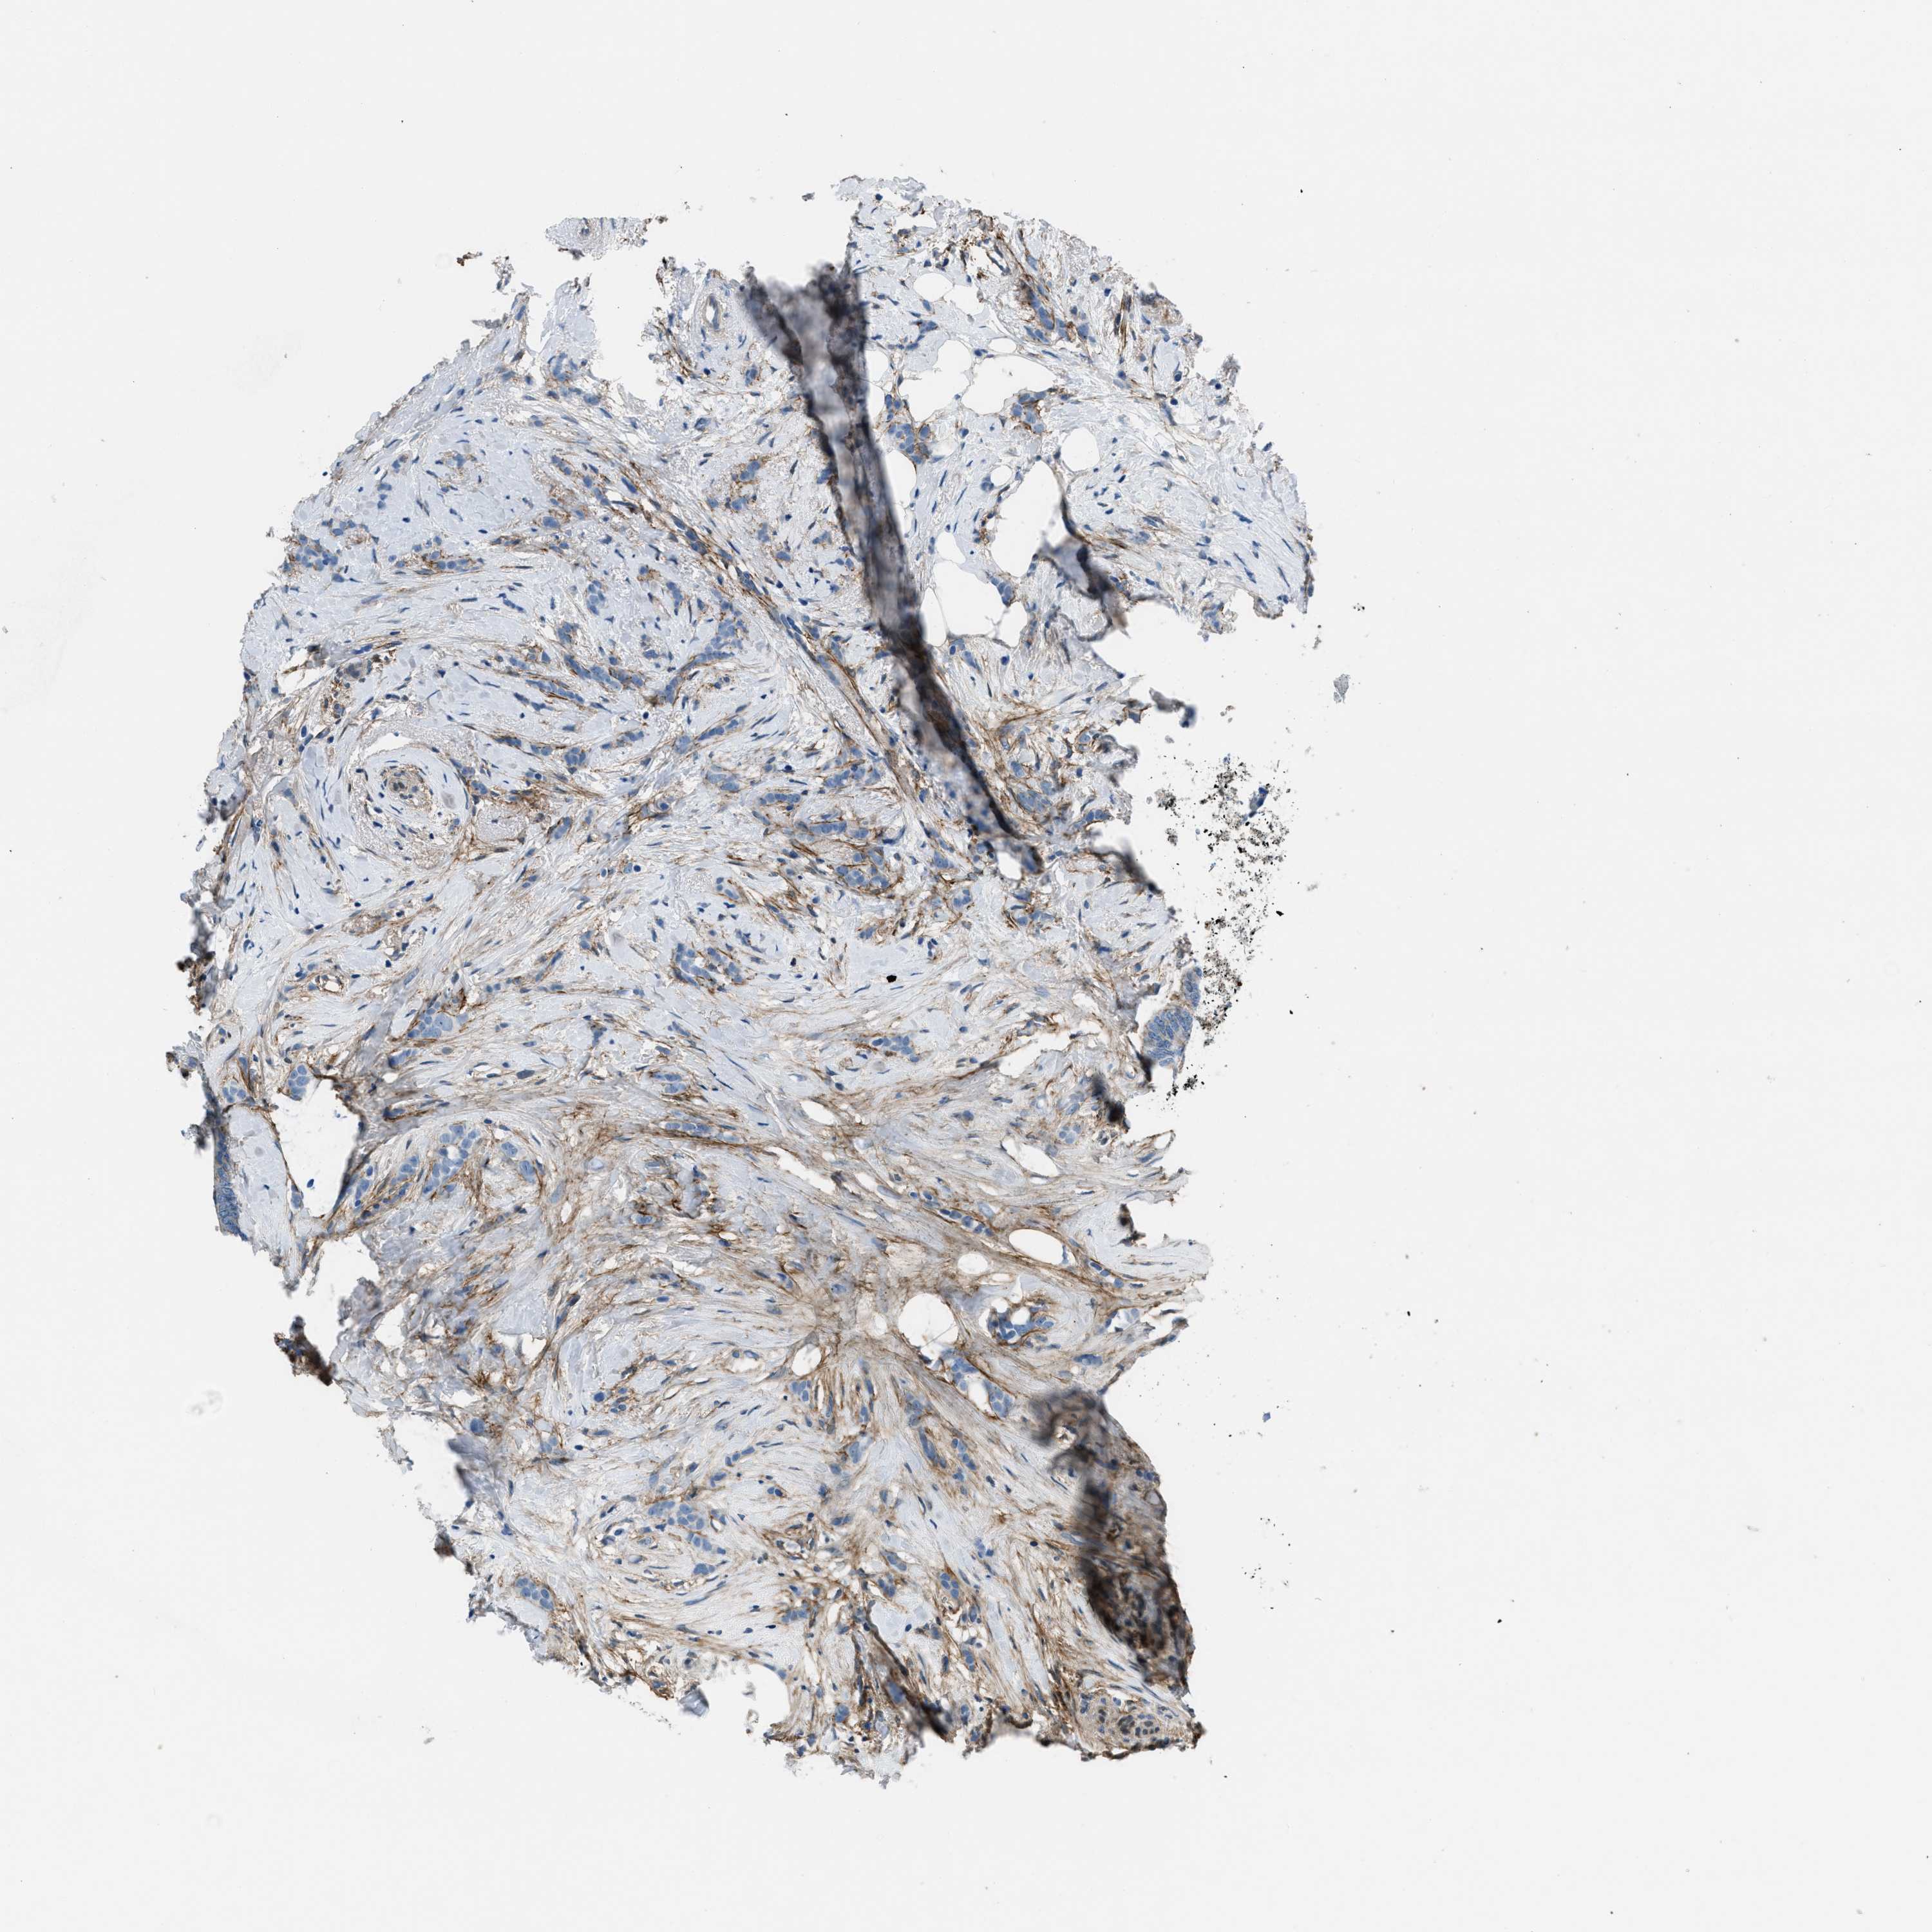

BRCA TCGA BRCA VALIDATION PROTEIN EXPRESSION